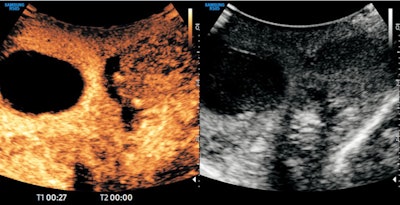

Ultrasound capabilities were "ever-evolving," with many different techniques combining to achieve a patient diagnosis, so-called "multiparametric" ultrasound, he continued. Moreover, this was accomplished at lower cost and patient morbidity than any other imaging modality.

He described the benefits and growing capabilities of ultrasound, including contrast-enhanced techniques and "exciting" developments in hepatic care, for measuring the quantity of fat and stiffness in patients' livers.